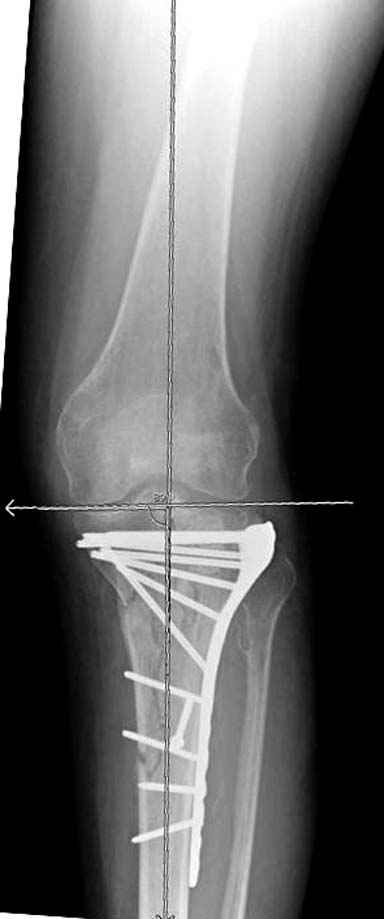

На вашем место я бы подождал с фиксацией до готовности кожных покровов, и за это время можно было подобрать соответствующий фиксатор, т.е более длинная пластина снаружи и медиальная пластина на апексе перелома как подпорка. Здесь приемлем как раз минимальный доступ.

Если там действительная импрессия, пустое место без структуральных заполнителей, кость или синтетические материалы, не восстановится, а образуется коллапс, и ось конечности поведет после нагрузки. Кроме того там возможно "болт стяжка"?, в медиальной стороне выступает за кортекс, можно было укоротить! Потом создается впечатление, что не соответствуют мыщелки большеберцовой и бедренной костей? Покажите снимок.

Здесь пару случаев для сравнения,...в первых 1-4 слайдах метод фиксации одним фиксатором, как видно после 8 месяцев сохранилась ось. С 5 по 9 вариант двумя пластинами...